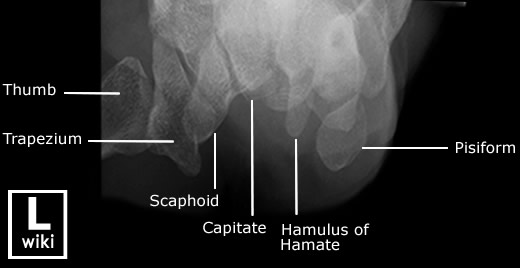

1) http://www.wikiradiography.net

| [Anatomy] Wrist(손목) (0) | 2024.01.15 |